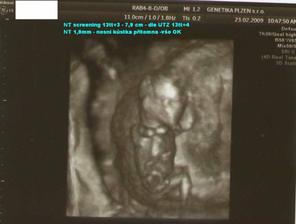

23.2.09 - NT screening I. trimestru Genetika Plzeň

23.2.09 - NT screening I. trimestru na Genetice v Plzni - NT 1,9mm, nosní kůstka přítomna,

mimi má 7,9 cm(CRL), celkem i s nožičkama 12cm, vše OK, placenta vzadu(OK) - komplet výsledek: negativní (hurááááááá)